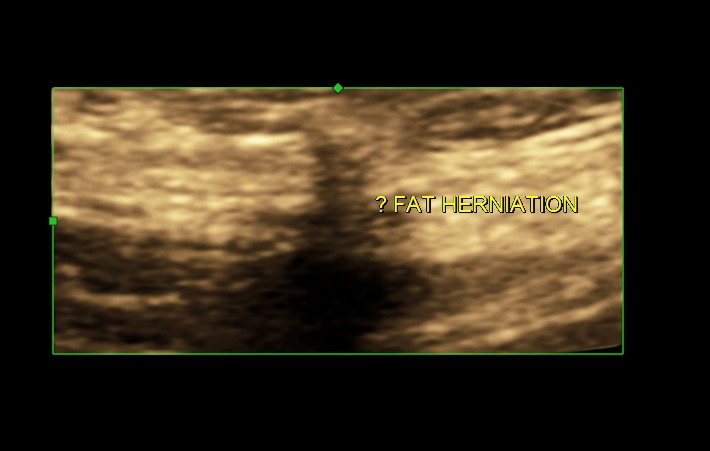

the next image is a 3 D reconstruction.